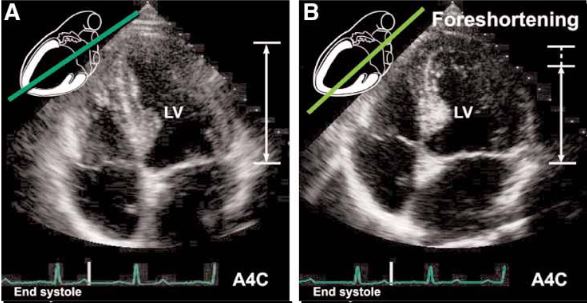

We are training an AI to automatically detect and assess the degree of foreshortening in echocardiographic images, specifically in the apical four-chamber (A4C) view.

Visual Examples

Examples of normal apical view and foreshortening